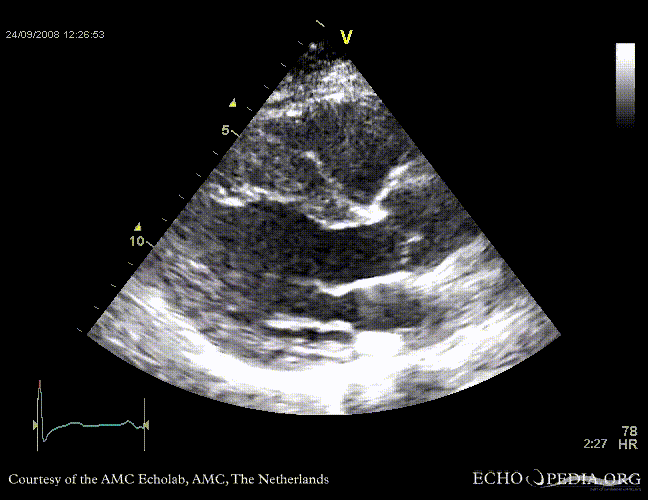

PSAX through aortic valve, clearly showing four valve leaflets PSAX through aortic valve, clearly showing four valve leaflets